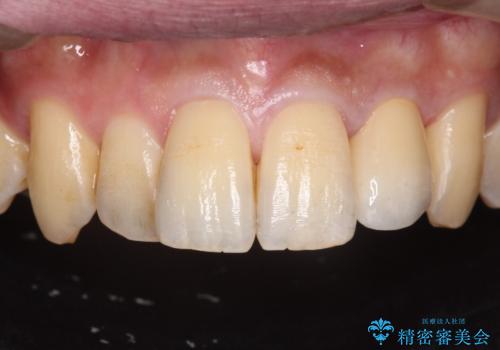

前歯のセラミック治療

- 左の前歯が黒いとのことで来院。

1番目の歯は小さい虫歯があったのでプラスチックの樹脂で治療をしました(保険内)。

2番目の歯は二箇所虫歯があり、プラスチックの樹脂で治療するとつぎはぎみたいになってしまうので、

白い被せ物(ジルコニアクラウン)で治療しました。

自然な被せ物が入り、大変満足して頂けました。